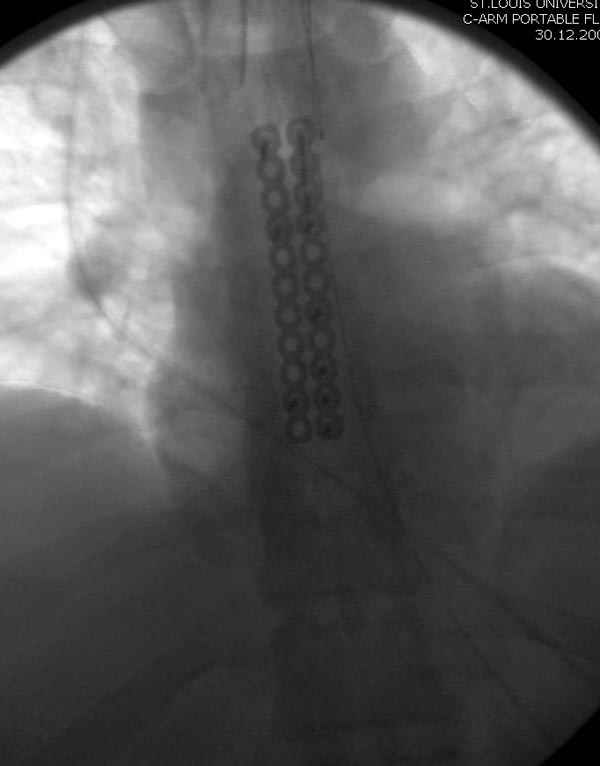

Пару лет назад коллега из грудной хирургии направил больного с хроническими жалобами на боли по поводу ложного сустава грудины.

Оперировали вместе с грудным хирургом и в нашем случае главной причиной была болезненность. Во время операции приняли все меры предосторожности недопущения прокола средостения (см. на 4 снимке близкий контур сердца!!)

Ложный сустав зафиксирован двумя пластинами 2.4 мм (locking plate) позаимствованными из челюстно-лицевой хирургии, с костной пластикой, все остальные пластины мне показались слишком толстыми, грубые для грудины или отсутсвовали возможности создания угловой стабильности.

Рентген снимки во время операции и последние сделаны на днях.